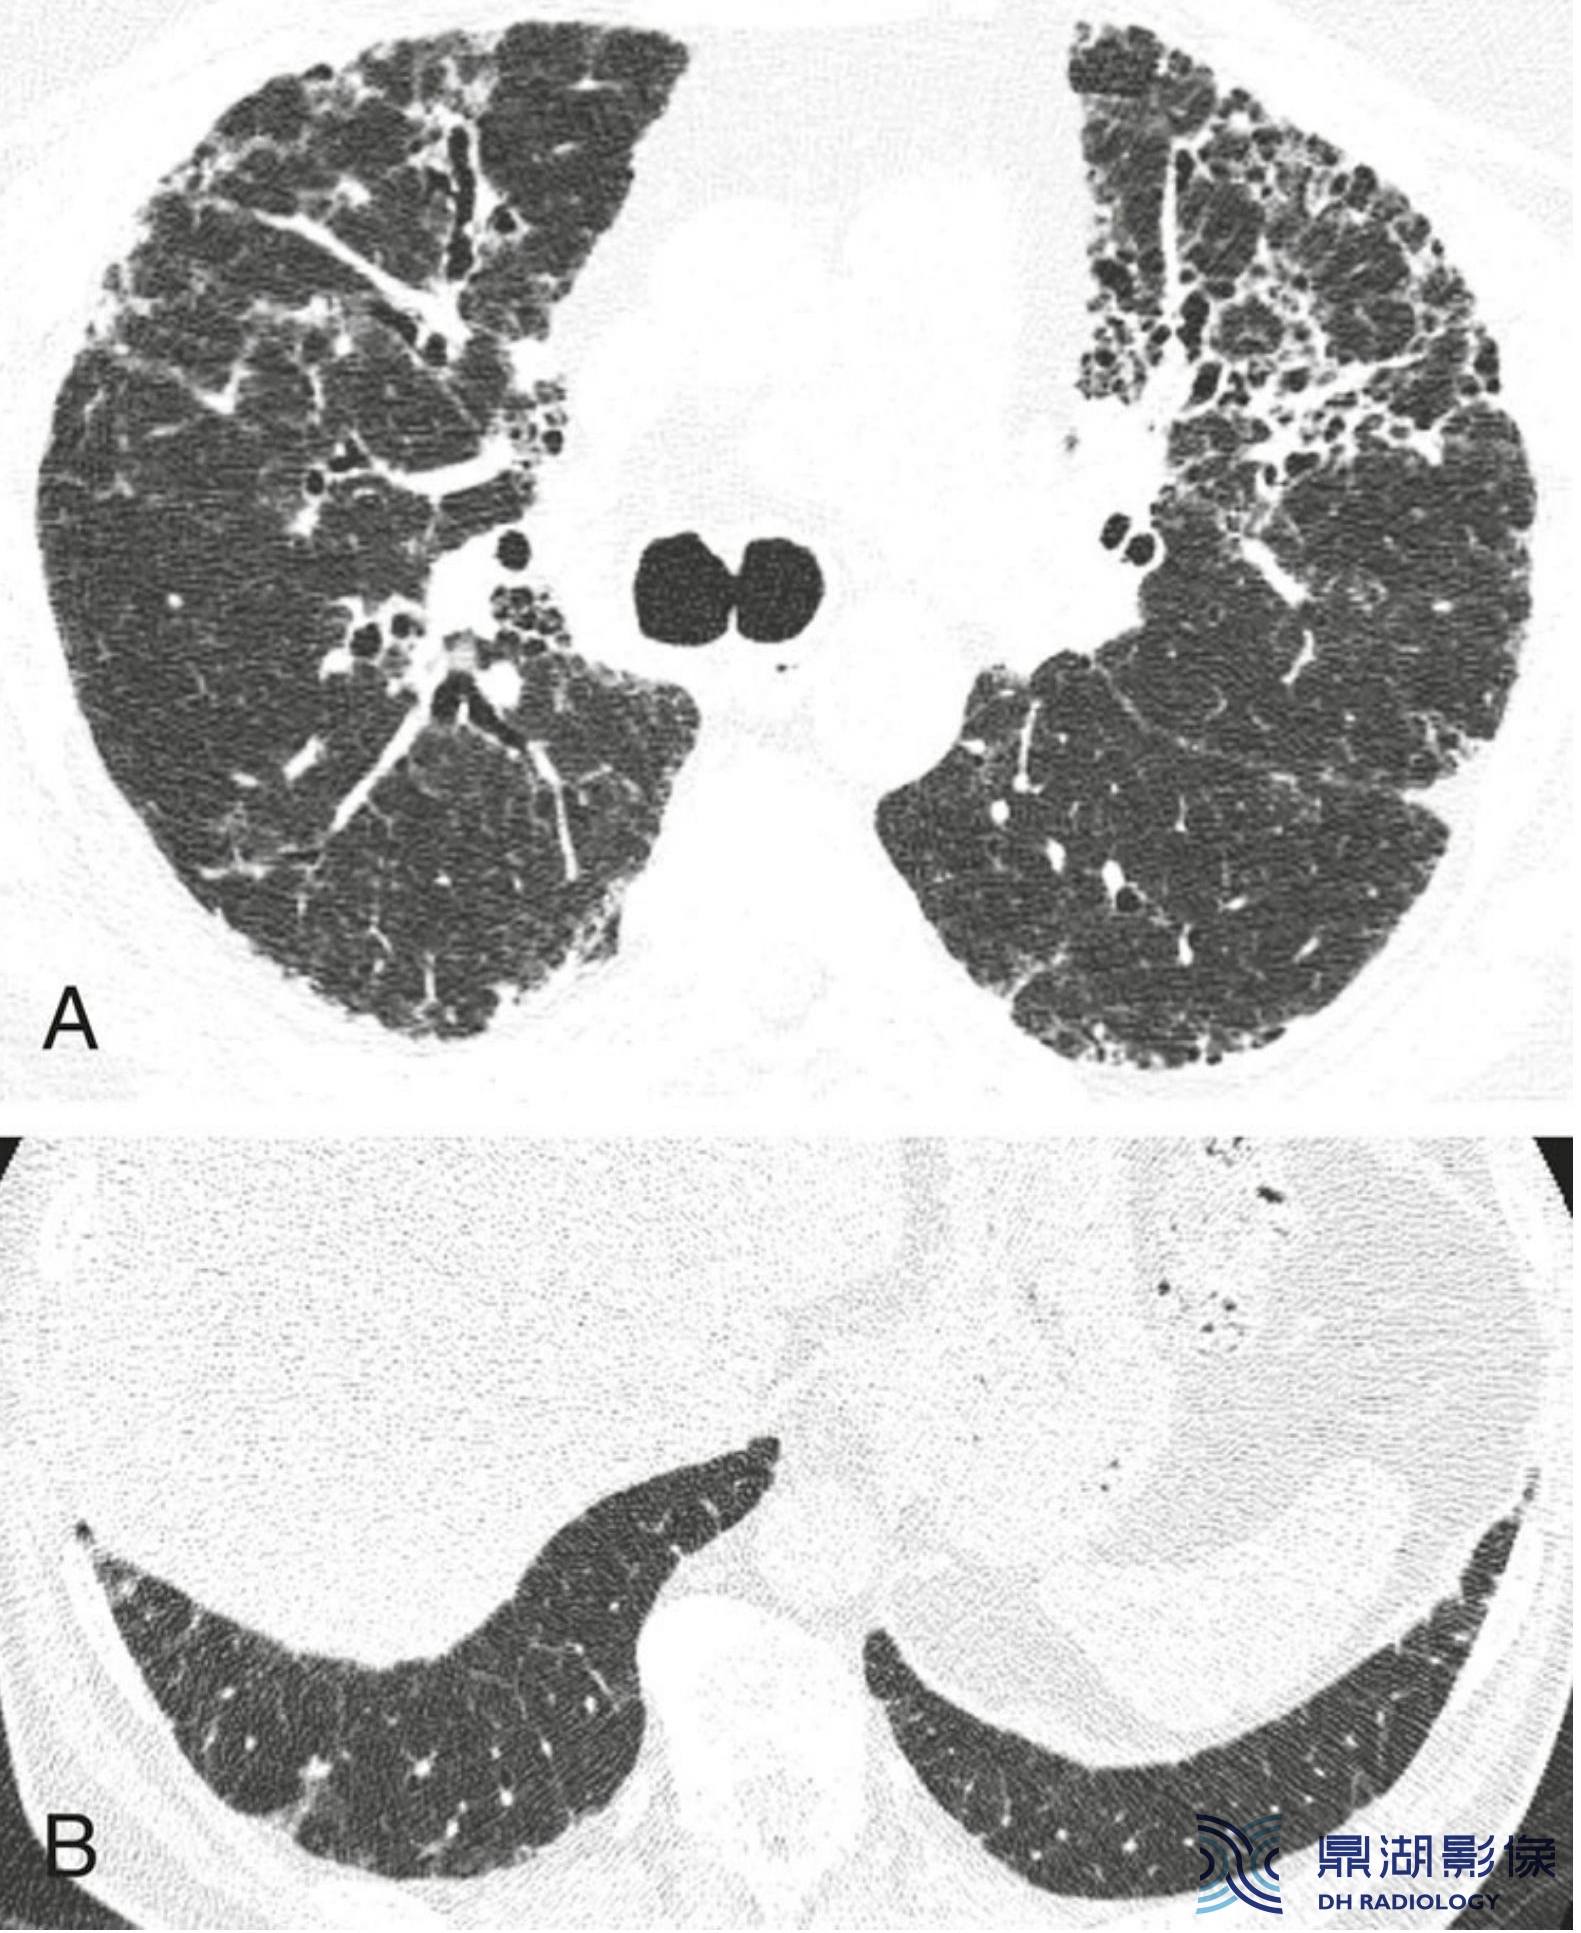

炎症与纤维化的HRCT不同表现。

间质性肺炎表现为不同程度的炎症和纤维化;A和B. 2例结缔组织病患者的非特异性间质性肺炎。

A.HRCT显示GGO,无明显的纤维化征象,提示潜在可逆的炎症性病变;

B.HRCT显示牵拉性支气管扩张(箭)及不规则网状影的纤维化征象,提示对治疗不敏感的肺部瘢痕。